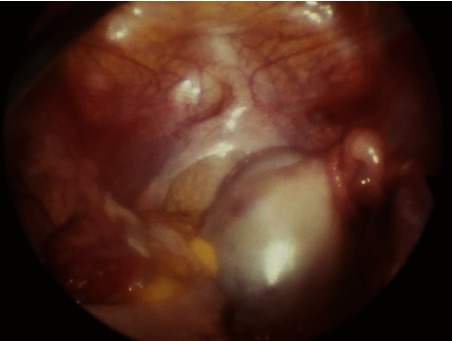

A case report of a premenarcheal patient with ovarian torsion and mullerian agenesis is presented. A 12-year-old prepubertal girl is presented with severe right lower quadrant abdominal pain and mild rebound. Laparoscopy showed mullerian agenesis and twisted right adnexa. Detorsion and cystectomy of the right ovary were done, and the ovary was fixed to the pelvic sidewall. The postoperative course was uneventful. An association between the lax attachment of the adnexa and torsion may be a contributing factor in this condition.

Abstract Image